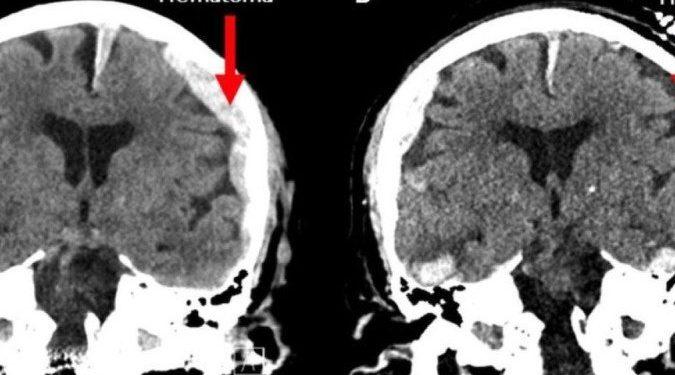

Zemmar e sua equipe advertiram que conclusões amplas não podem ser tiradas de um estudo com apenas uma pessoa. O fato de o paciente ser epiléptico, com o cérebro com hemorragia e inchado, complica ainda mais as coisas.